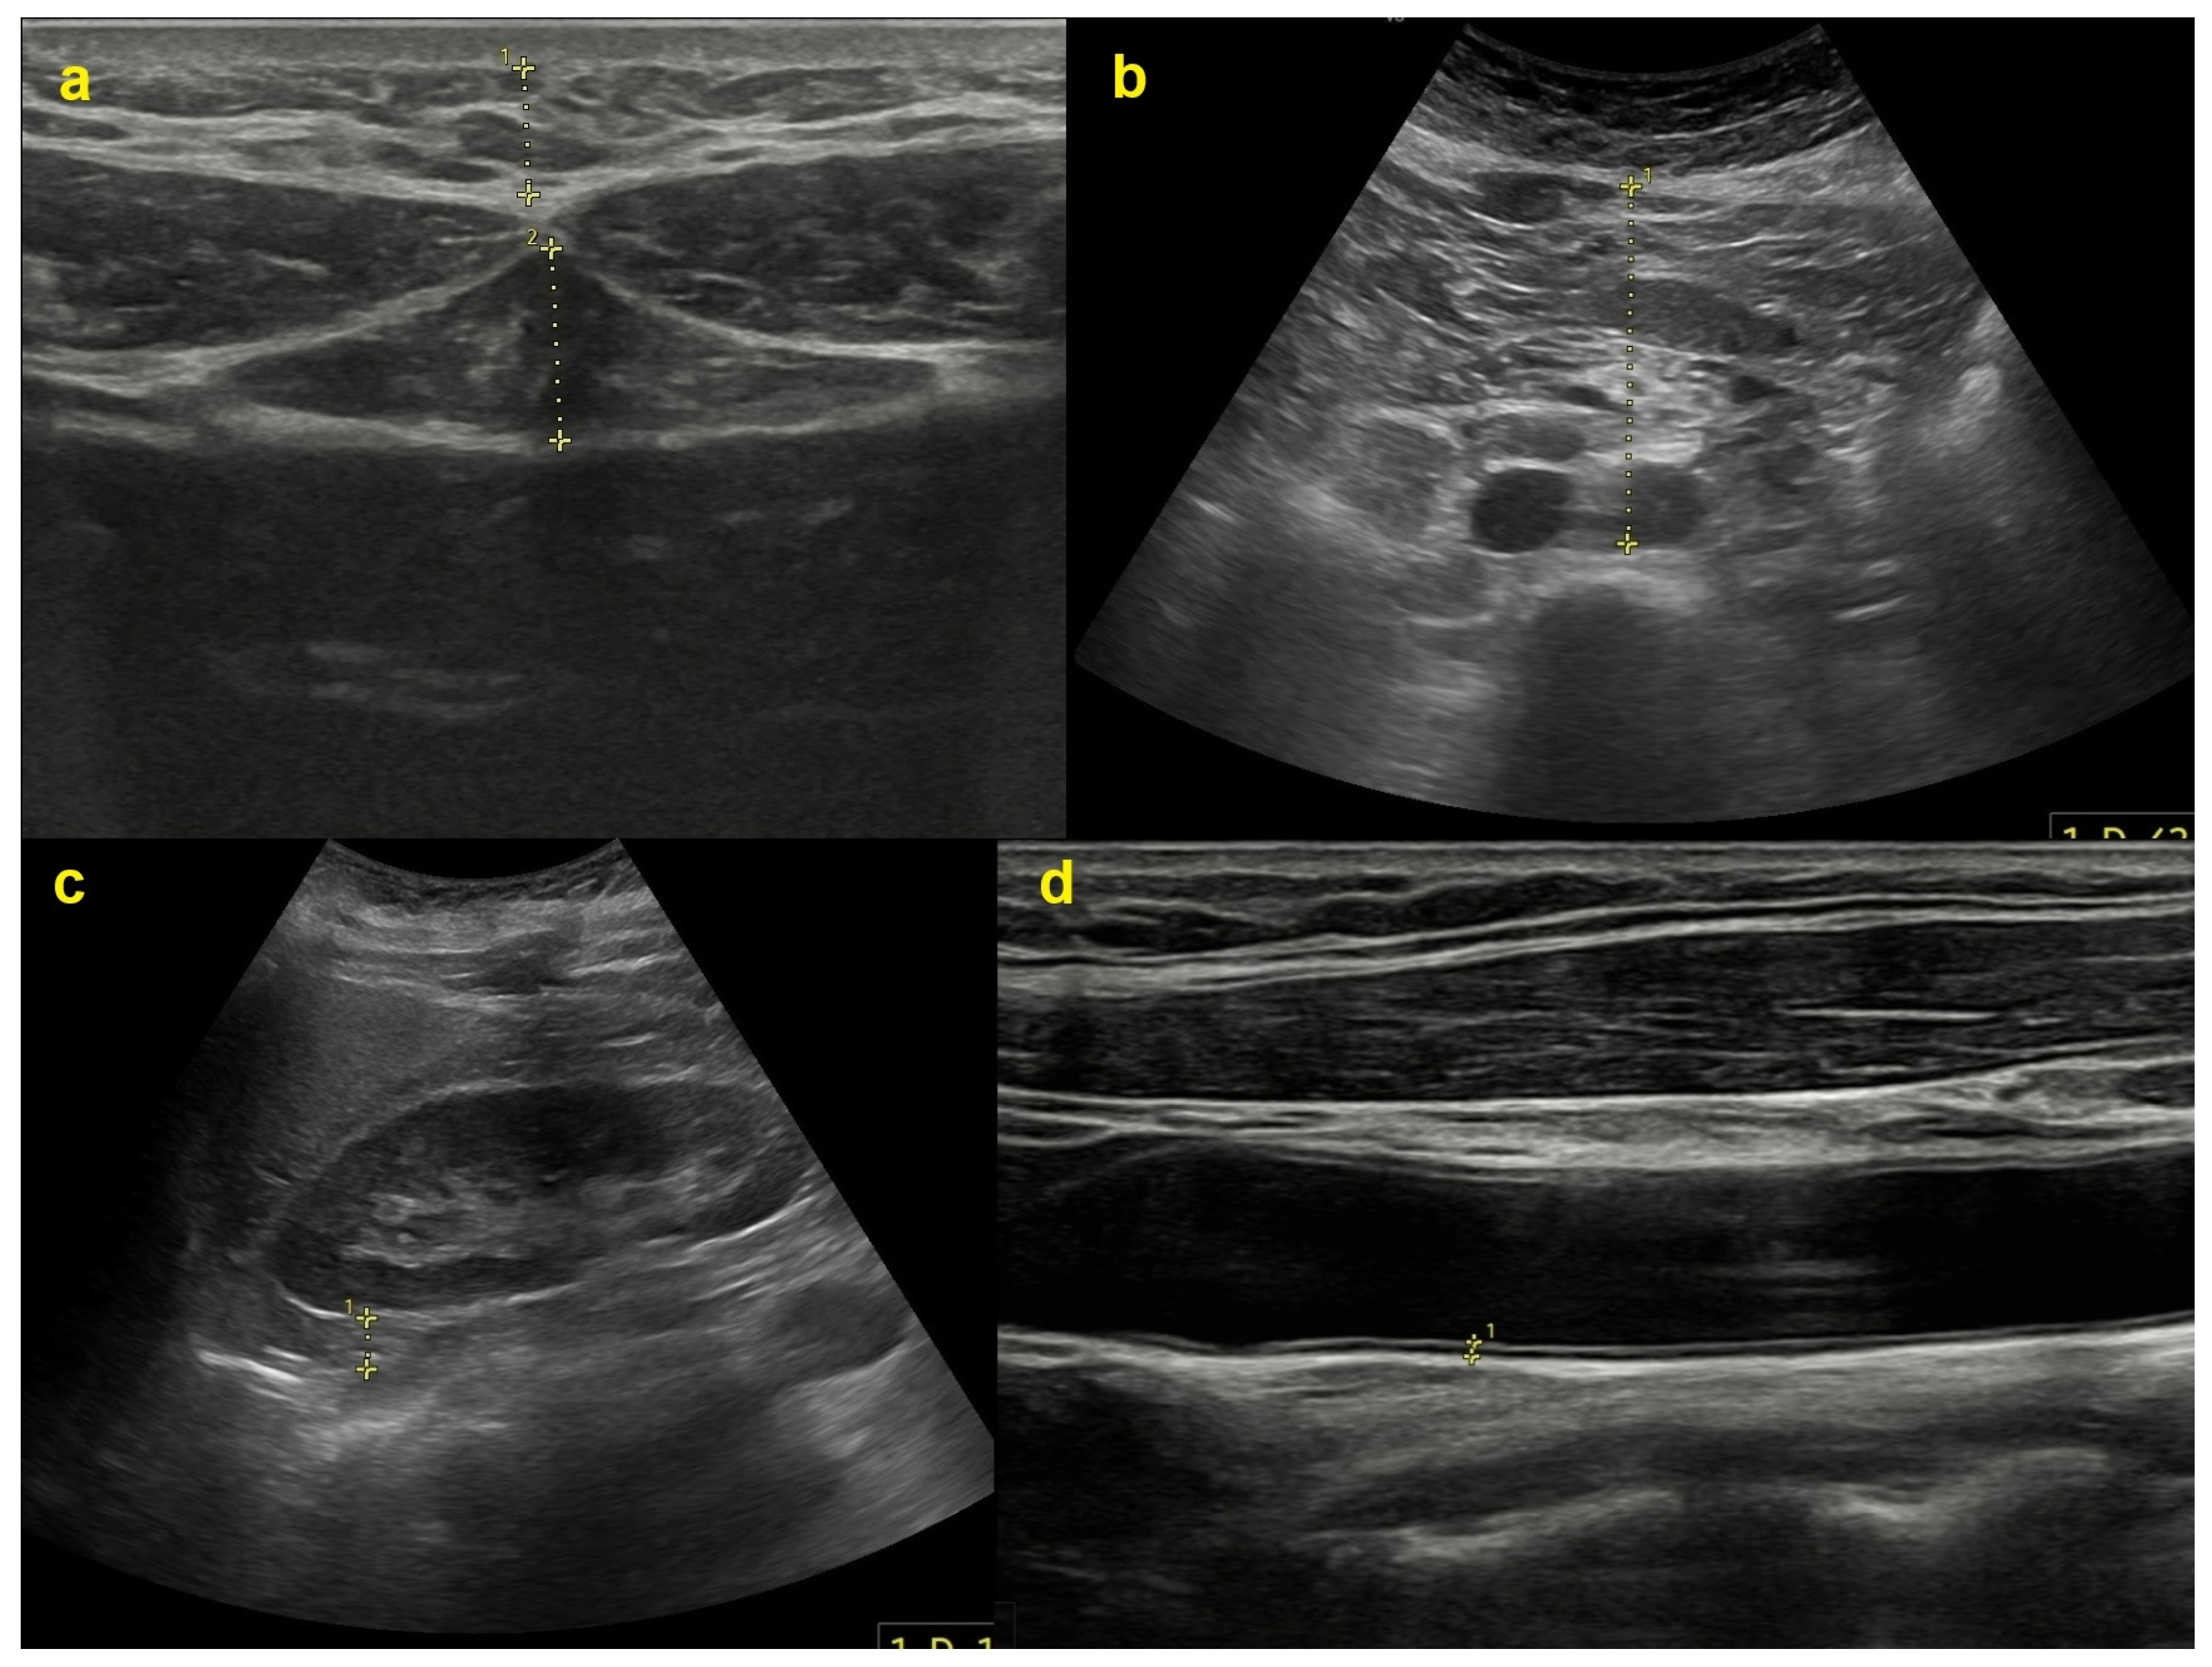

2.2. Imaging Procedures